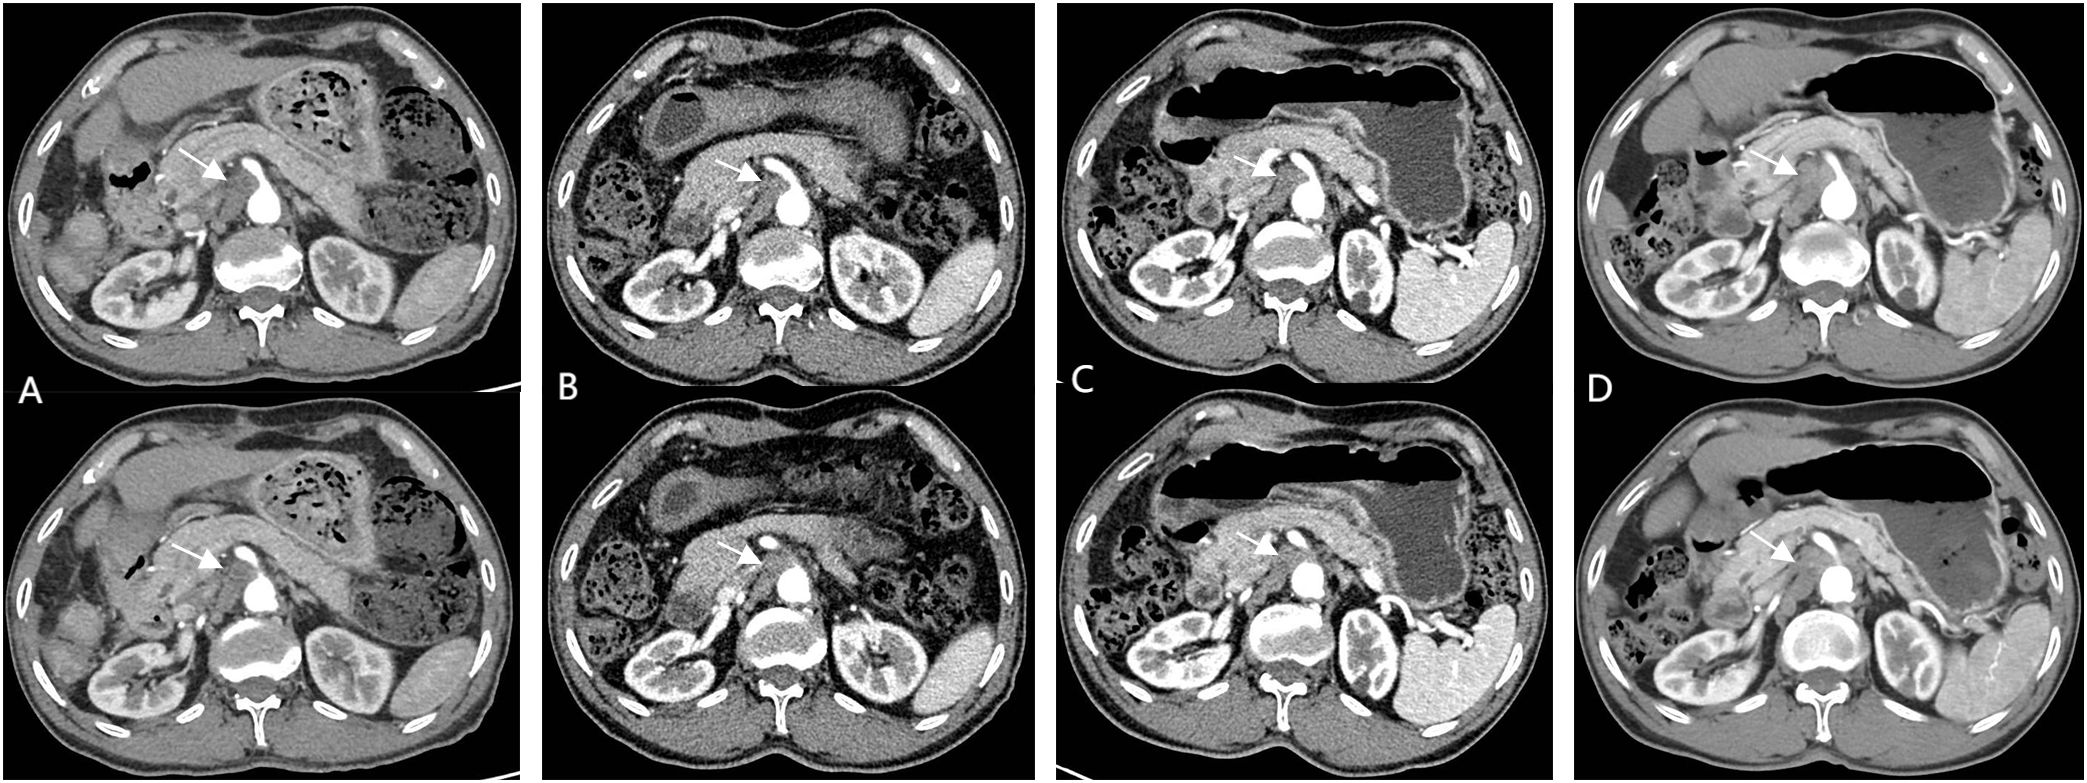

Figure 4

Figure 4. Follow-up CEMRI scans reveal complete resolution of previously enlarged lymph nodes, with images (A) (13 months post-operative), (B) (15 months post-operative), and (C) (18 months-postoperative) documenting temporal changes.

The patient returned for follow-up 45 days after discontinuation of the medication. A contrast-enhanced abdominal MRI revealed complete resolution of the previously enlarged SMLNs (Figure 4A). Subsequent tri-monthly follow-up evaluations demonstrated no recurrence of mesenteric lymphadenopathy (Figure 4B). The most recent surveillance conducted on February, 2025 (18 months since disease onset) showed no evidence of tumor recurrence (Figure 4C). The diagnostic and therapeutic timeline is summarized in Supplementary Figure 2.